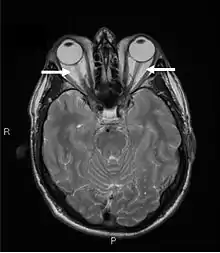

Orbital imaging is an interesting tool for the diagnosis of Graves' ophthalmopathy and is useful in monitoring patients for progression of the disease. It is, however, not warranted when the diagnosis can be established clinically. Ultrasonography may detect early Graves' orbitopathy in patients without clinical orbital findings. It is less reliable than the CT scan and magnetic resonance imaging (MRI), however, to assess the extraocular muscle involvement at the orbital apex, which may lead to blindness. Thus, CT scan or MRI is necessary when optic nerve involvement is suspected. On neuroimaging, the most characteristic findings are thick extraocular muscles with tendon sparing, usually bilateral, and proptosis.